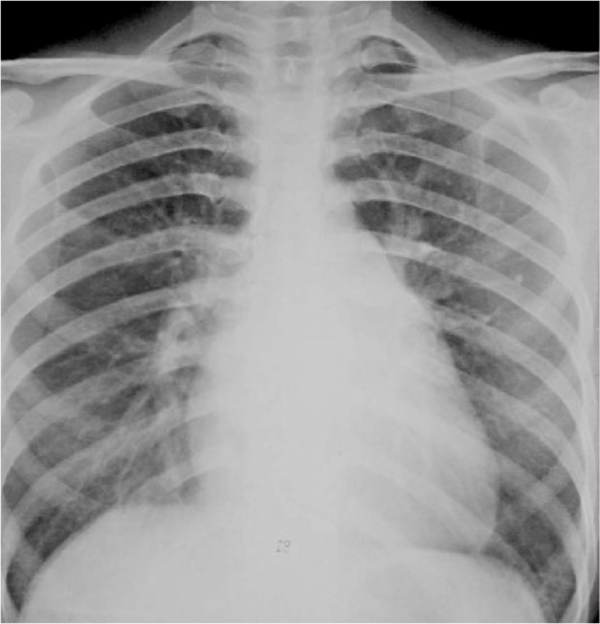

图2-22二尖瓣型心脏(梨型心)2.

图2 胸片正位:梨形胸廓,心影增大